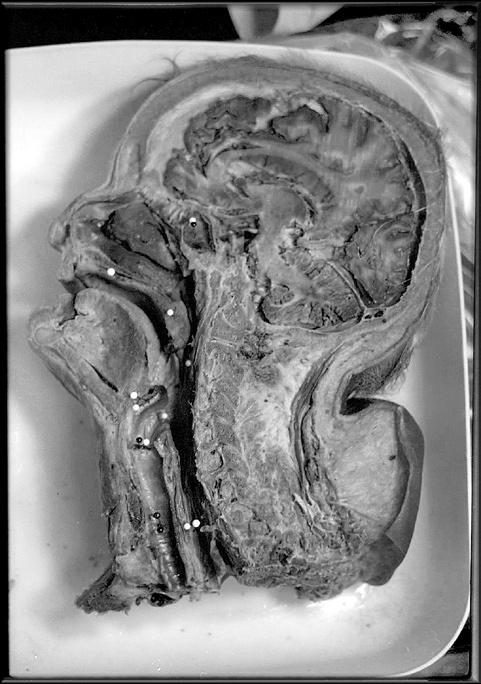

UVM faces a decline in body donations to science BY KEN PICARD

The University of Vermont wants you — or, more accurately, your remains once you’ve shuffled off this mortal coil.

It’s not the kind of information medical schools typically advertise in a local newspaper. Then again, this isn’t a typical year. For the first time in anyone’s memory, UVM has a critical shortage of cadavers. And if the number of donations doesn’t pick up by January, the university will have to start hunting around for dead bodies.

Rod Parsons chairs UVM’s anatomy and neurobiology department. Appropriately enough, he’s also director of the university’s Anatomical Gift Program — a position he’s held for 30 years. Parsons notes that donations are down this year by about half: from an average of 35 to 45 bodies annually to 20. That could create a problem for students in the spring semester.

Compounding the situation is the fact that demand for cadavers has actually grown as UVM has expanded its medical training and research programs. The College of Medicine has 114 students, up from 75 when Parsons became chair in 1979. That number doesn’t include the students who are working toward graduate degrees in neuroscience, those training to become physical therapists, the residents who need corpses on which to

practice new surgical procedures, or other medical researchers working at the Burlington campus.

Moreover, Parsons notes, most of UVM’s donated bodies come from within the state, and Vermont’s population growth hasn’t kept pace with the school’s burgeoning demand for corpses.

In fact, it can be considerable, depending on where the person dies and who handles the body. According to a 2007 price survey of local funeral homes conducted by the Vermont Funeral Consumers Alliance, the cost of body donations ranges from $525 to $1790, depending on the funeral home. And that figure doesn’t include other fees tacked on by the mortician, such as get-

THE COST OF TRANSPORTING THE DECEASED TO THE MEDICAL SCHOOL IS STILL INCURRED BY THE NEXT OF KIN. IN TOUGH ECONOMIC TIMES, THAT EXPENSE MAY BE TOO MUCH FOR SOME VERMONTERS

Parsons isn’t certain what explains the record-low body count, though he has a few theories. It may be due to an encouraging trend: Vermonters are healthier and living longer. Or it could be a matter of chance: The number of anatomical donations fluctuates from year to year, ranging from 32 to 50. This year may be a statistical aberration.

Another possible factor is that anatomical gift programs have gotten a bad rap in recent years owing to a few “bad apples.” Although UVM’s program has a spotless ethical record, the same can’t be said for all medical schools. For example, in 2007, the director of UCLA’s Willed Body Program was arrested for profiteering from the sale and transportation of bodies and parts. Such revelations, though rare, do little to instill public trust in an industry that is largely unregulated.

ting copies of the death certificate or storing the body overnight.